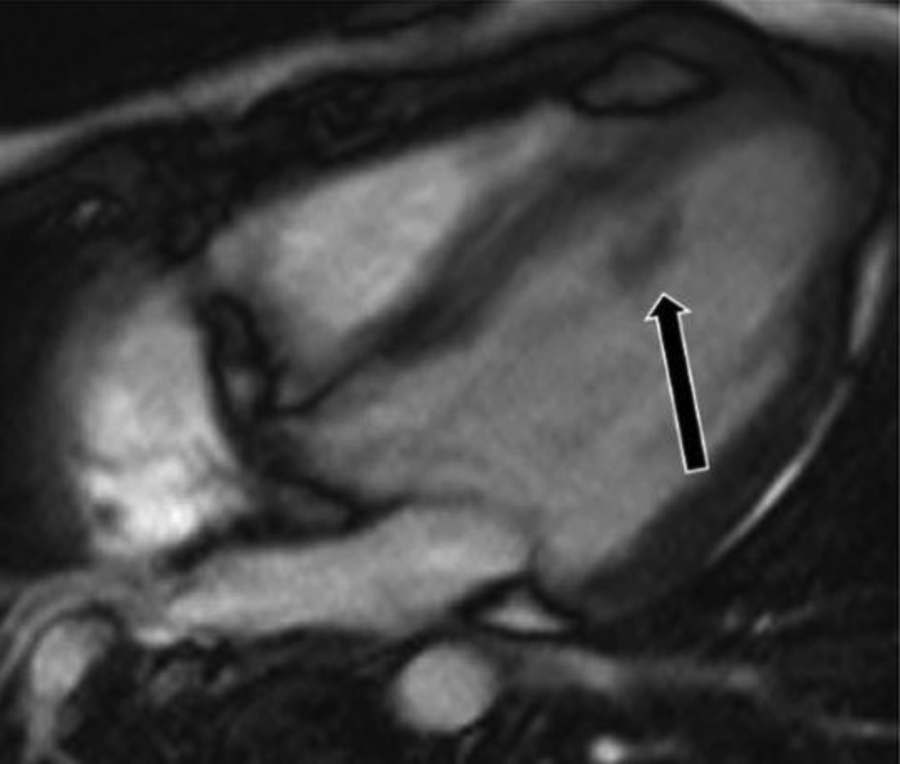

Figure 9

A 71-year-old female with aortic valve fibroelastoma. (A) This mass showing hyper-intense signal on T2weighted, dark blood, double inversion recovery fast spin echo images (red arrow).